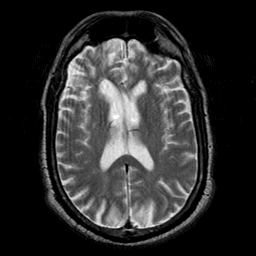

Subacute Stroke overlay -- Slice #13

[Home][Help][Clinical] Slice 13